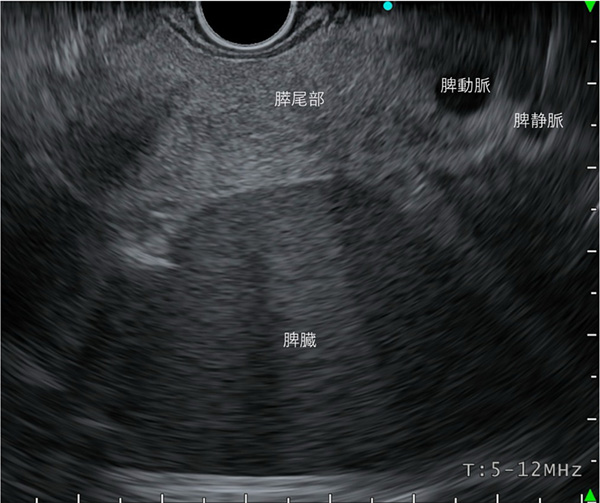

〈胃内操作による観察〉

脾門部まで観察できれば、膵尾部末端まで観察したことになります。一般に、腹部エコーではこの領域は描出不能と呼ばれる部位です。